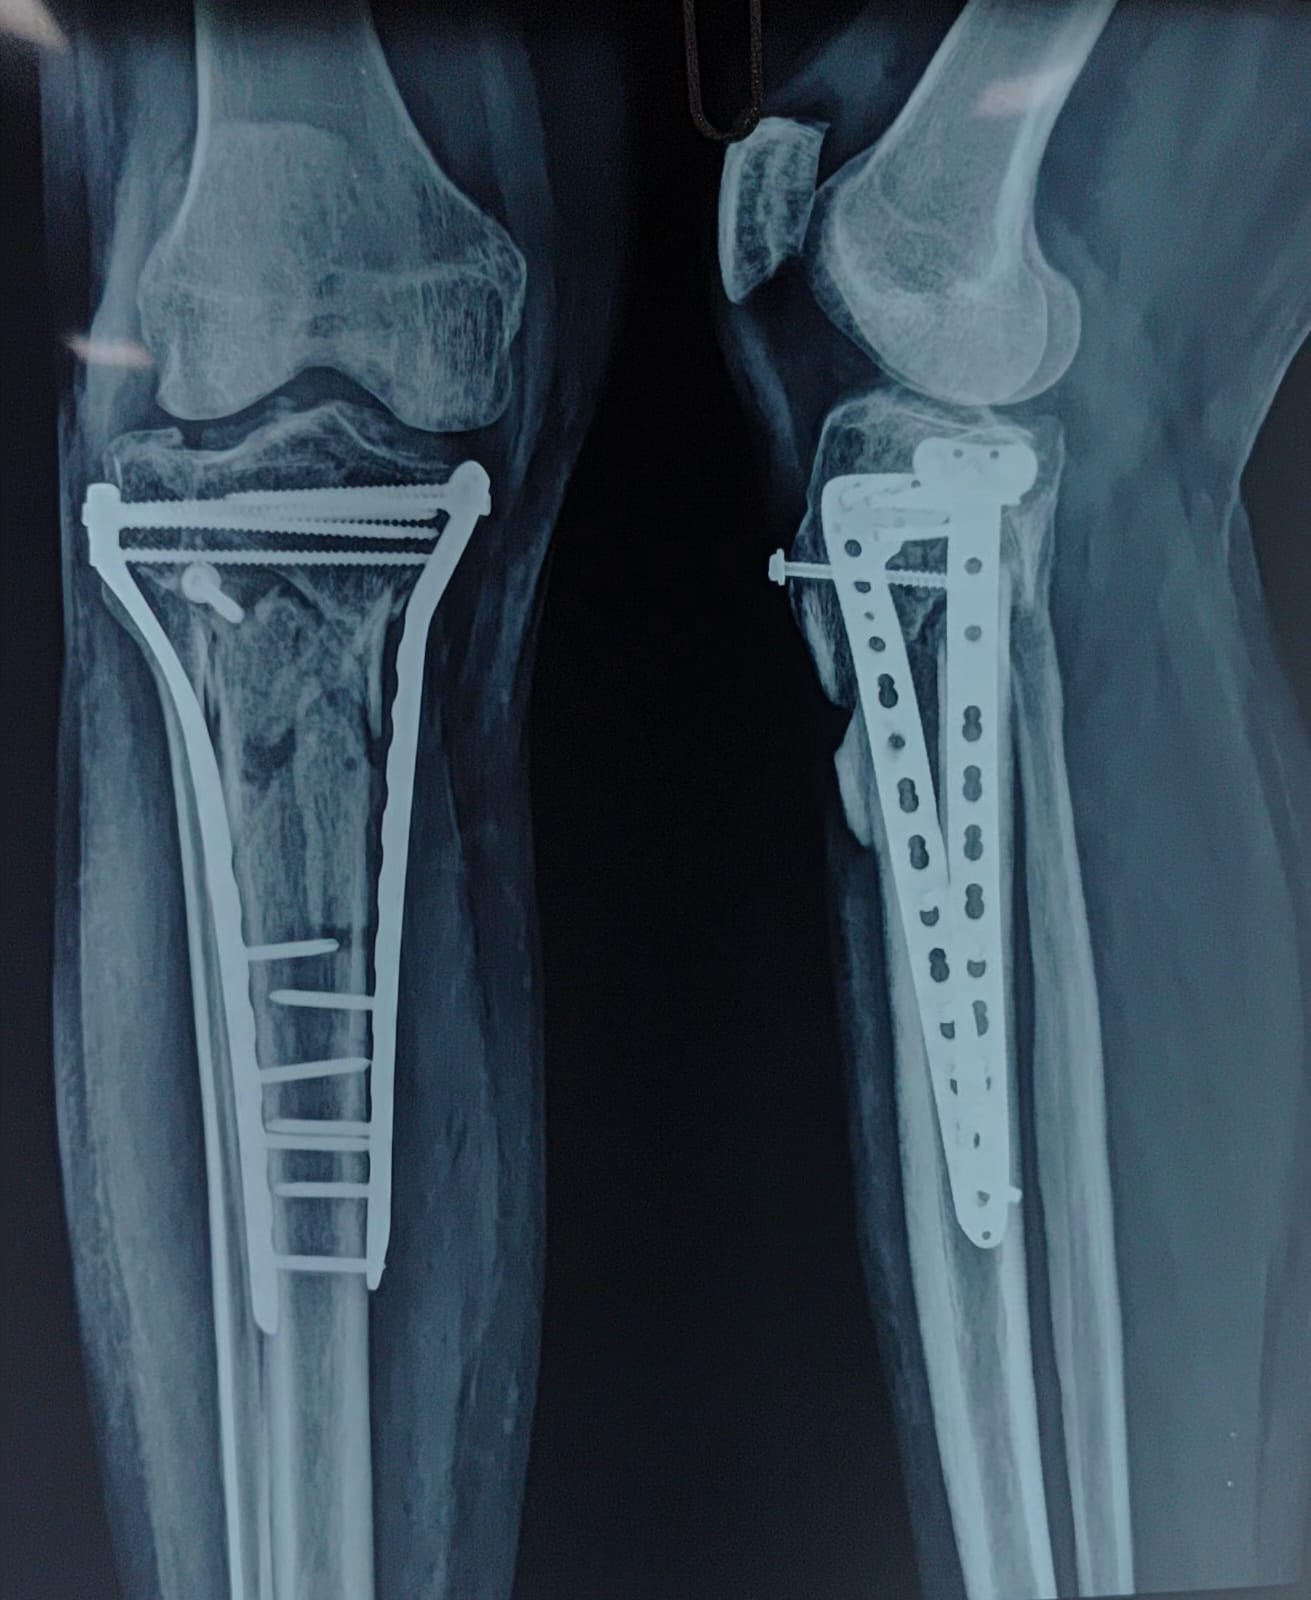

Sunshine Ortho Pain Superspeciality Hospital is the Best Multispeciality Hospital, Orthopedic Hospital in Wakad, Hnjewadi, PCMC and Pune. We are specialized in Orthopedic Surgeries, Robotic Joint Replacement Surgery, Hip and Knee Replacement Surgery, Complex Trauma And Pelvi Acetabular Surgery, Spine Surgery, Sports Medicine And Arthroscopy, Regenerative Therapy/Prolotherapy, Shoulder Surgery, Knee Surgeries, Foot And Ankle Treatment in Wakad, Hinjewadi, PCMC and Pune.